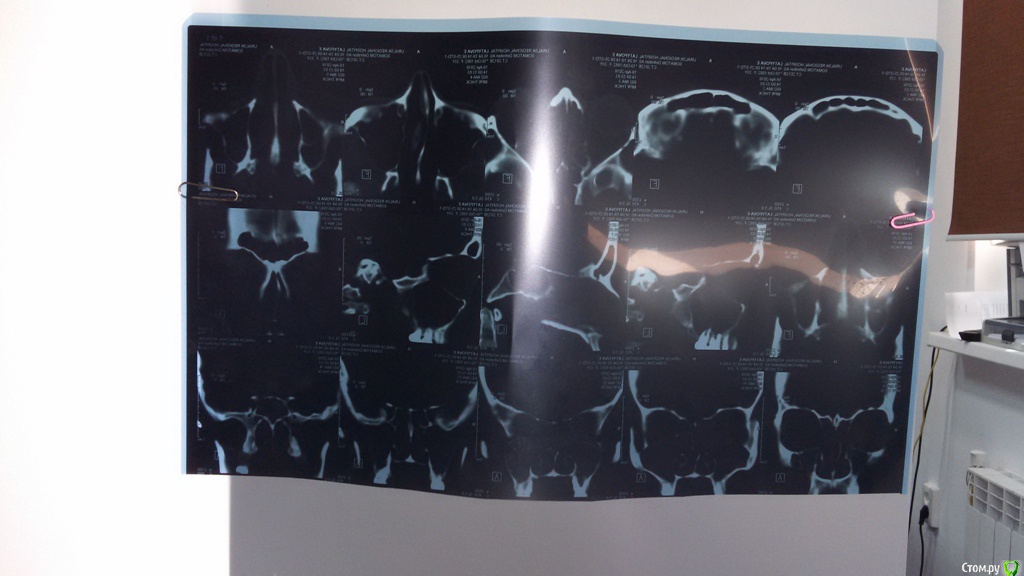

VELICOPTER Опубликовано 16 августа, 2016 Автор Поделиться Опубликовано 16 августа, 2016 Посмотрите пожалуйста это фото. Ссылка на комментарий

DmitrySH Опубликовано 16 августа, 2016 Поделиться Опубликовано 16 августа, 2016 Увы, совсем не то Ссылка на комментарий